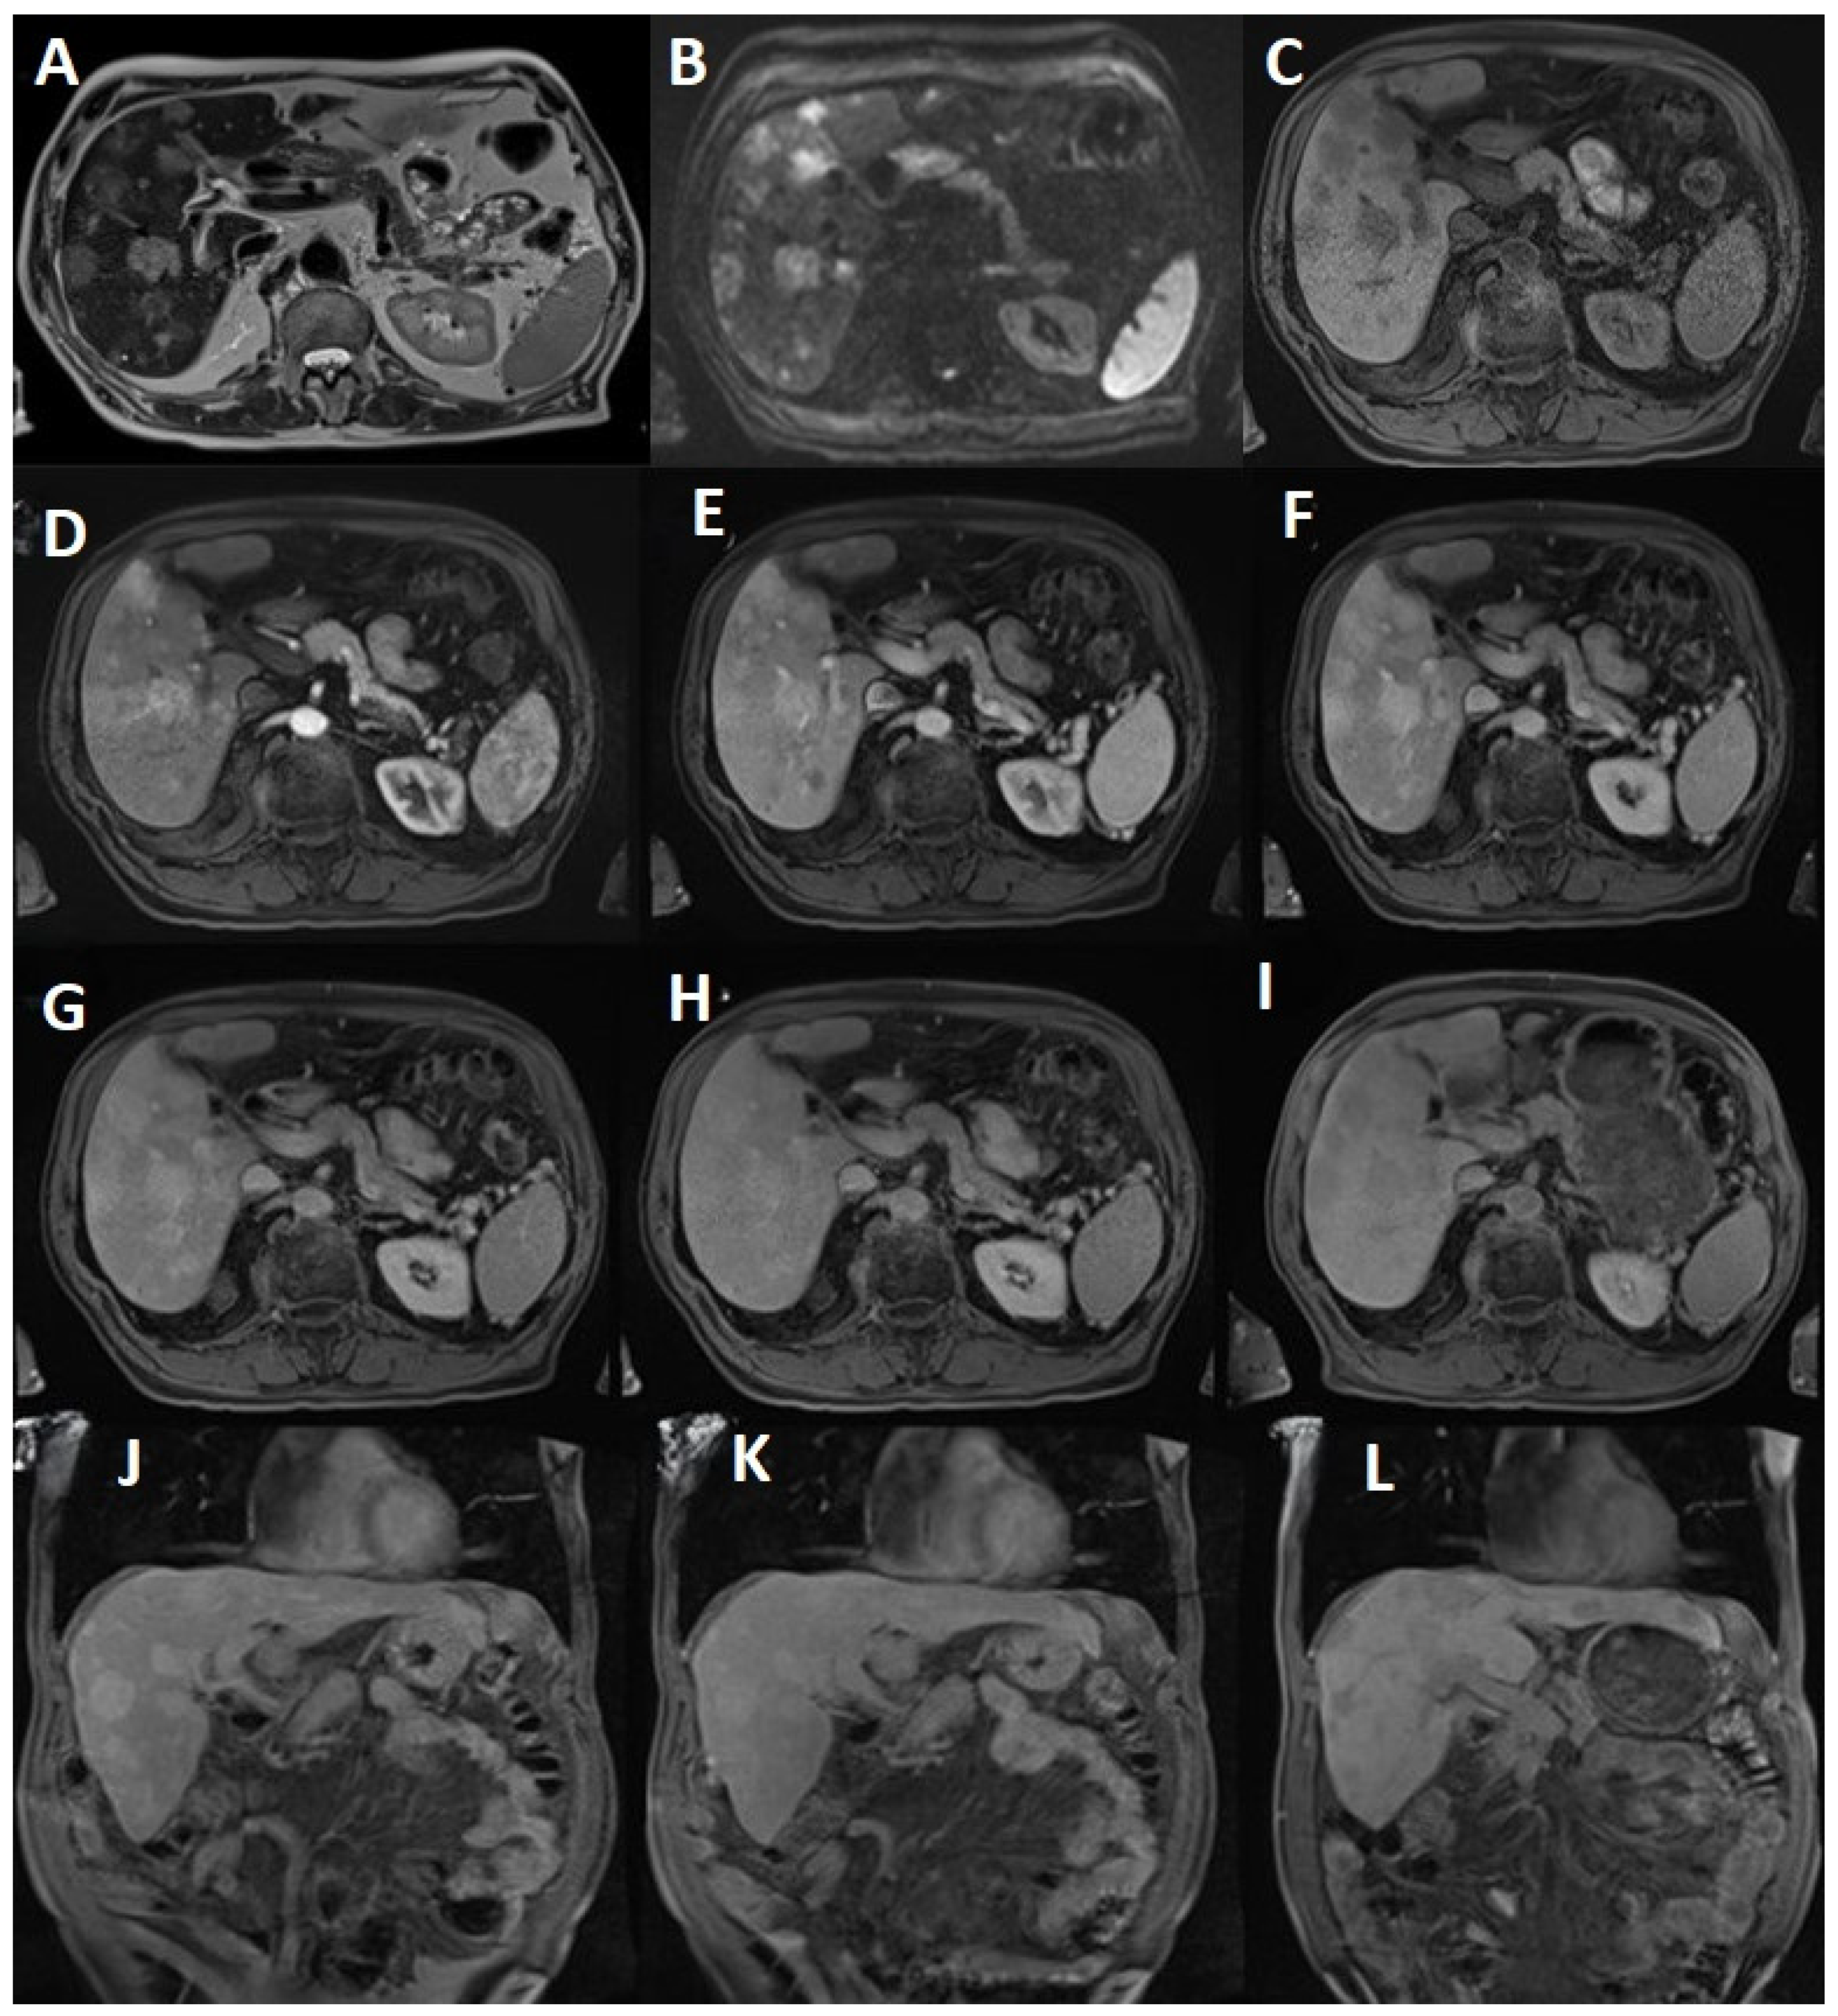

2.2. Standard MRI Liver Protocol

2.3. MRI Dynamic Three-Phasic Scanning

2.4. Delayed Multiphase Scanning